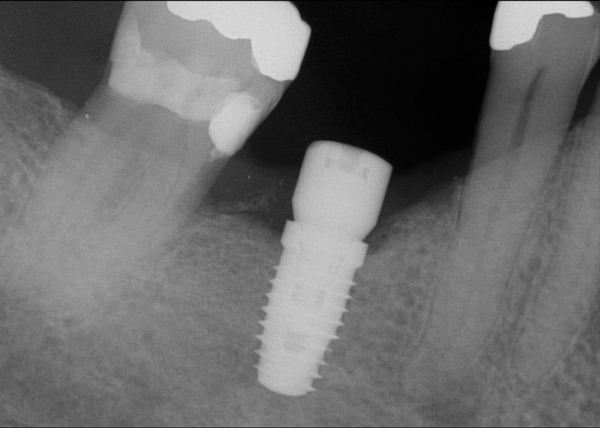

Fig 11. An implant was placed in regenerated bone.

Figure 11